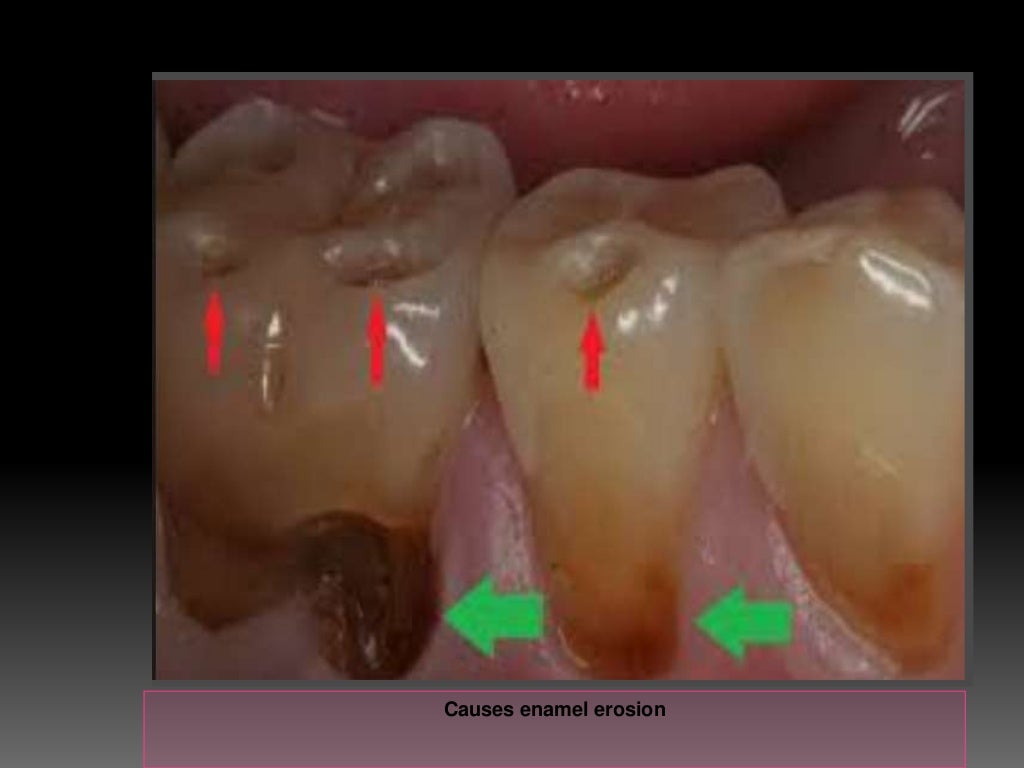

Reasons For Tooth Enamel Loss